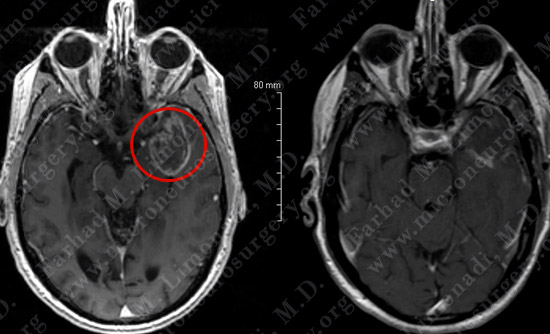

Post-op Imaging

Before Operation After Operation

Post-op day 1 MRI shows complete resection of the tumor with no injury to surrounding neurovascular structures.